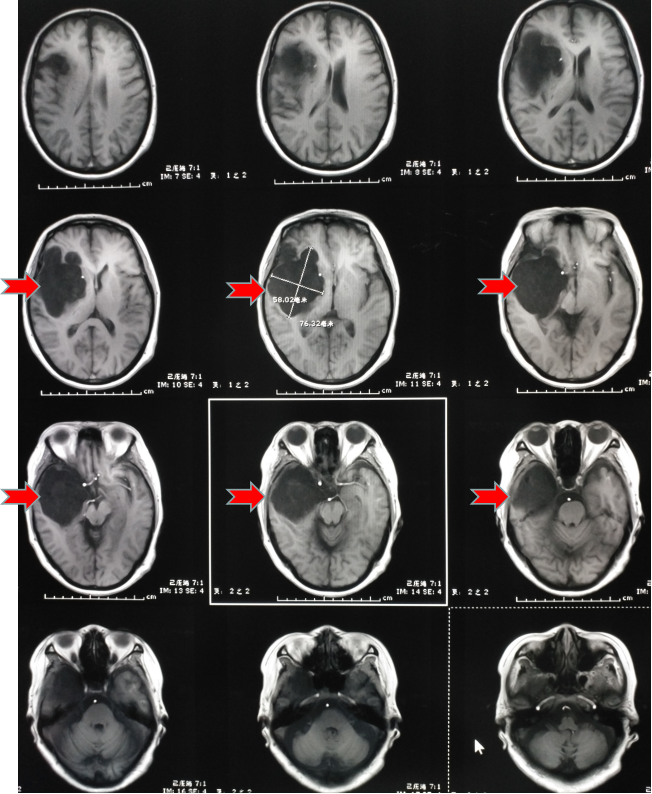

第二天趕緊到醫(yī)院看了一下,醫(yī)生說這是癲癇,隨后給她開了“丙戊酸鈉”長期口服,用藥后仍然每年有1-2次發(fā)作,大多是在晚上,有時(shí)即使沒有發(fā)生四肢抽搐,但有一種異樣的感覺。雖然這兩年很少發(fā)作了,但異樣感覺一直存在。今年她順利退休了,但教師的職業(yè)病——頸椎病卻讓他頸肩部以及上肢經(jīng)常麻木酸困,所以查了一下磁共振,確實(shí)存在頸椎病,但不需要手術(shù),只需保守治療即可。但意外的是發(fā)現(xiàn)了腦子里面長了個(gè)瘤子,大小約7厘米。

頭部磁共振提示腫瘤大小約7cm

一看片子,確認(rèn)是良性腫瘤,準(zhǔn)確點(diǎn)說應(yīng)該是一種叫做表皮樣囊腫的腫瘤,生長時(shí)間比較長,所以在早期很難發(fā)覺,經(jīng)常是在偶爾查頭部CT或者磁共振時(shí)發(fā)現(xiàn)。我給她說,這就是一直困擾她幾十年的病根所在,只要將它切除,她的癲癇和異樣感會(huì)逐漸消退,否則,隨著腫瘤增大,不僅會(huì)癲癇反復(fù)發(fā)作,而且會(huì)影響其他神經(jīng)功能??紤]再三,最終她還是選擇手術(shù)治療。